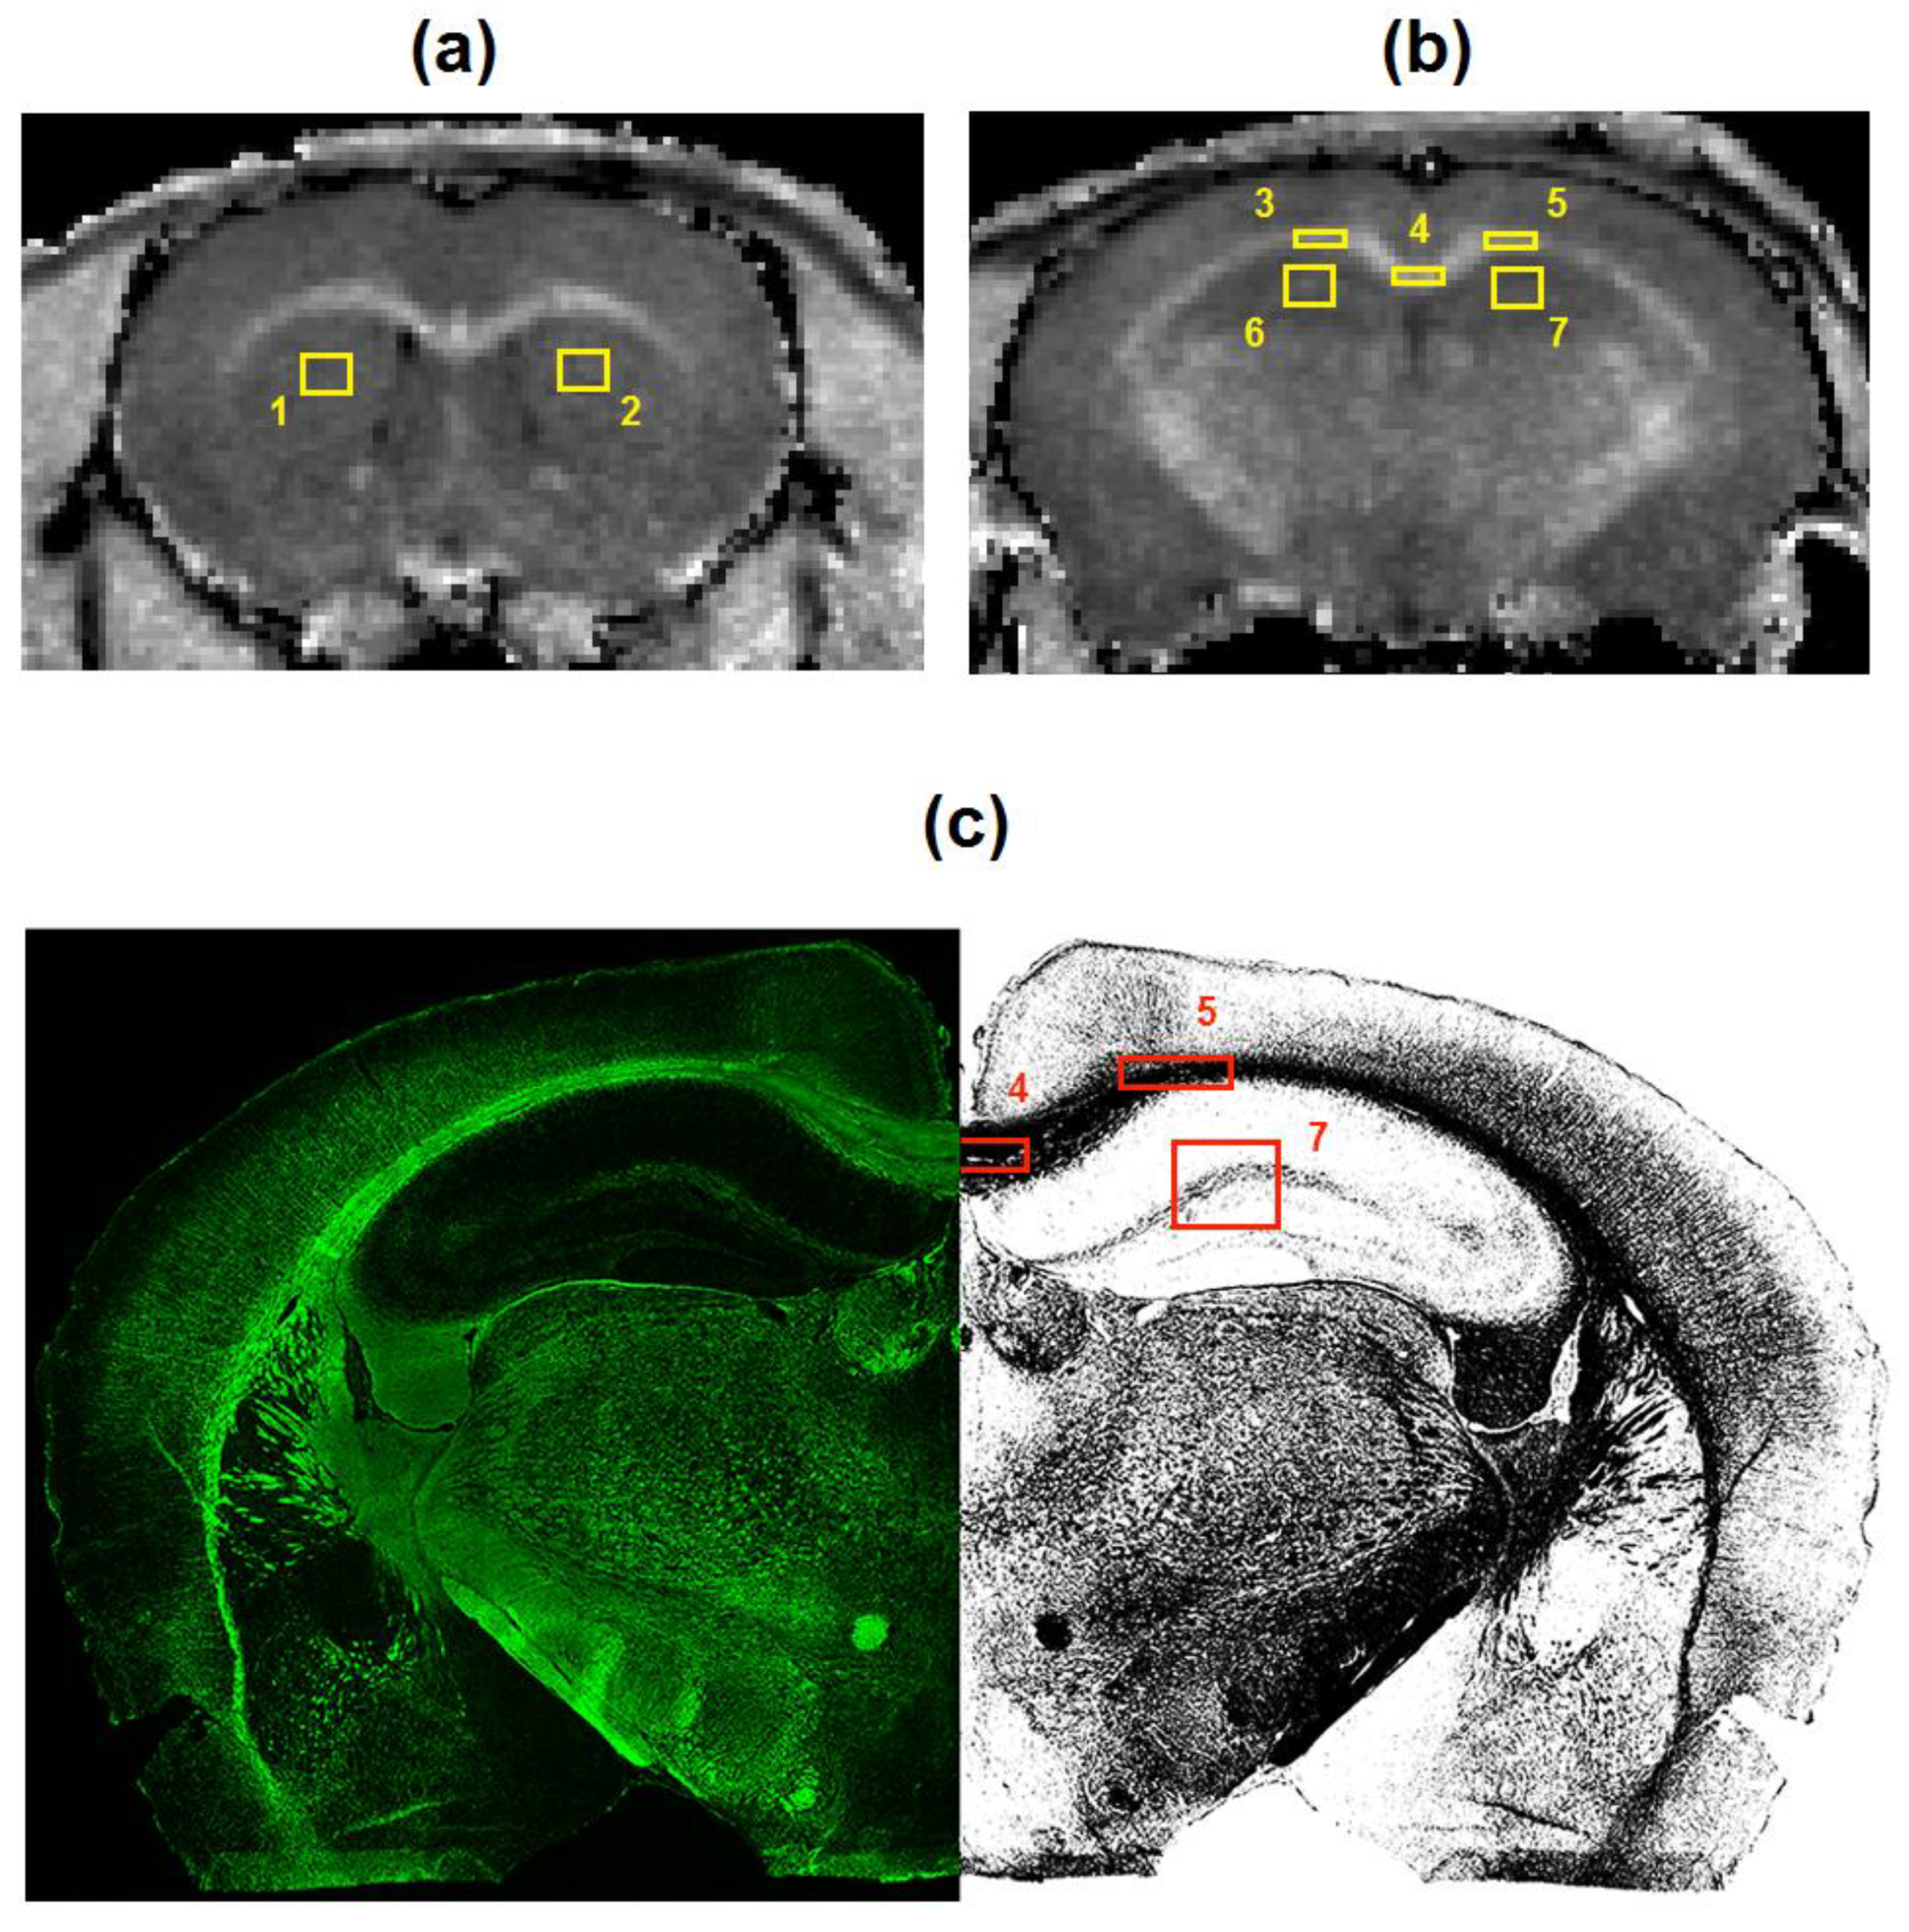

2.4. Image Analysis